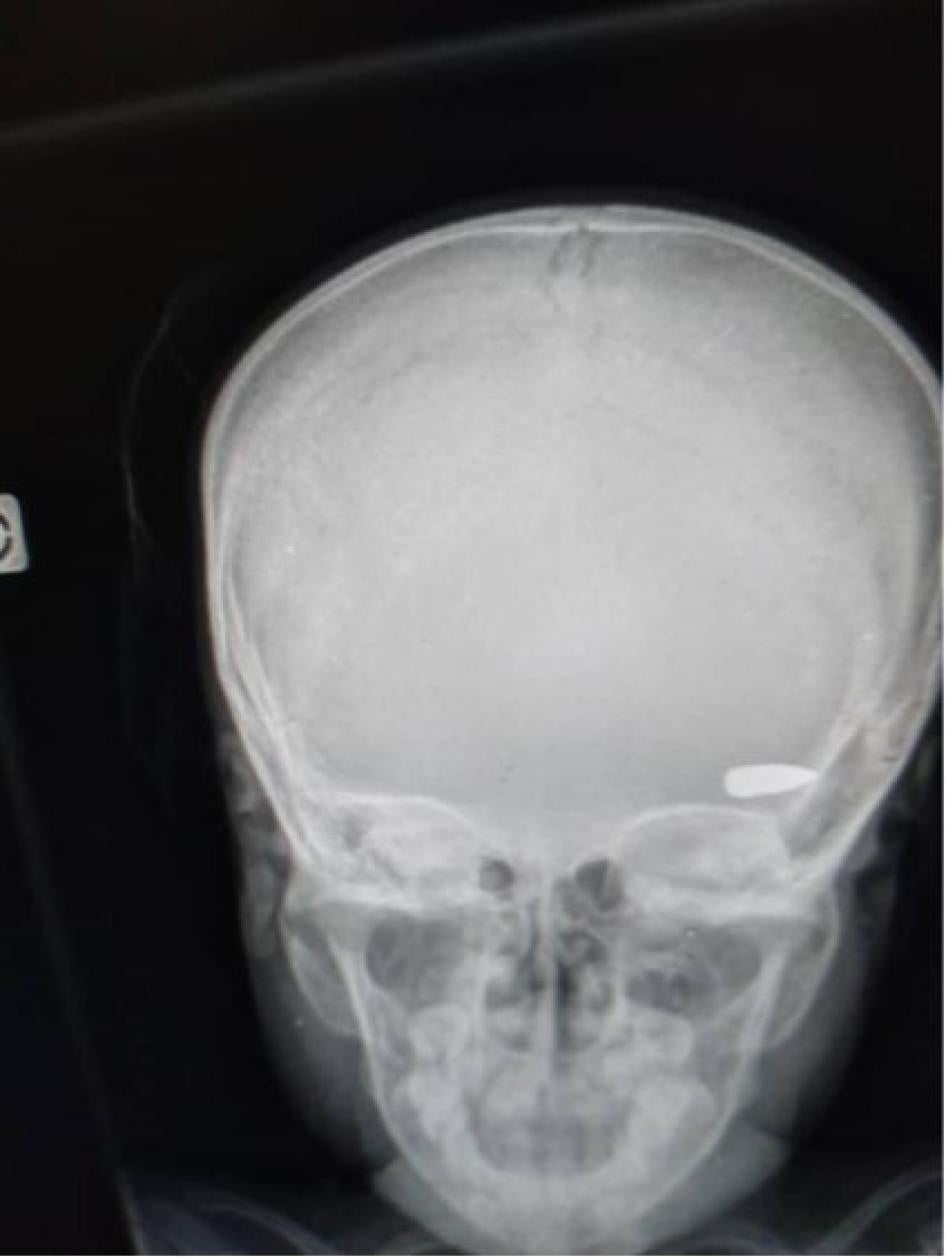

Al menos 45 víctimas murieron por heridas de bala, mientras que otras fueron atacadas con machetes y algunas fueron incineradas vivas dentro de sus casas. La mayoría de las personas que recibieron disparos fueron alcanzadas en la cabeza, el pecho o la espalda, y parecen haber sido el objetivo. Al parecer, dos fueron víctimas de balas perdidas mientras estaban dentro o justo fuera de sus casas, y una víctima recibió un disparo mientras huía de los enfrentamientos entre diferentes grupos criminales. En unos pocos casos, los familiares pudieron recuperar los cuerpos de sus seres queridos para darles sepultura. La mayoría de los cuerpos, sin embargo, fueron quemados en las calles o se los llevaron los grupos criminales[41].

Human Rights Watch documentó 35 asesinatos en esta zona, incluyendo los de 6 menores de edad, y 17 casos de violencia sexual. Adicionalmente, entrevistamos a cinco personas heridas de bala en Carrefour la Mort mientras eran tratadas en un hospital de Puerto Príncipe.